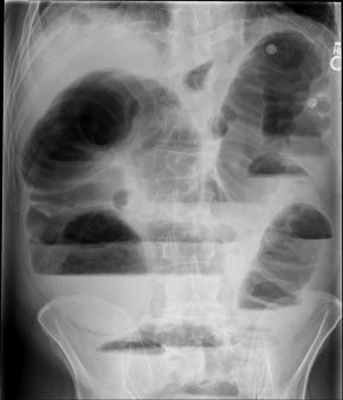

- Чаша Клойбера – горизонтальный уровень жидкости с куполообразным просветлением над ним, что имеет вид перевернутой вверх дном чаши. При странгуляционной непроходимости могут проявляться уже через 1 час, а при обтурационной непроходимости — через 3-5 часов с момента заболевания. Количество чаш бывает различным, иногда они могут наслаиваться одна на другую в виде ступенчатой лестницы.

- Кишечные аркады. Получаются, когда тонкая кишка оказывается раздутой газами, при этом в нижних коленах аркад видны горизонтальные уровни жидкости.

На рентгенограммах, полученных в положении стоя или лежа на боку, обычно видны горизонтальные уровни жидкости и газа (рис. 2). Рисунок 2. Обзорная рентгенограмма брюшной полости. Видны чаши Клойбера, уровни жидкости. Заполненные газом кишечные петли имеют вид опрокинутых чаш (чаши Клойбера). Они появляются при странгуляции через 1-2 ч после начала заболевания, при обтурации - через 3-5 ч. По размерам чаш Клойбера, их форме и локализации можно судить об уровне непроходимости.

При тонкокишечной непроходимости чаши Клойбера небольших размеров, ширина горизонтального уровня жидкости больше, чем высота столба газа над ним. Обычно наблюдается большое количество горизонтальных уровней с изменением их расположения в течение времени и перемещением жидкости из одной петли в другую. Горизонтальные уровни жидкости ровные. На фоне газа хорошо видны складки слизистой оболочки (складки Керкринга), принимающие форму растянутой спирали.

При непроходимости тощей кишки горизонтальные уровни жидкости локализуются в левом подреберье и эпигастральной области. При непроходимости в терминальном отделе подвздошной кишки уровни жидкости расположены в области мезогастрия.

При тонкокишечной непроходимости, кроме чаш Клойбера, на рентгенограммах видны растянутые газом кишечные петли, принимающие форму «аркад» или «органных труб», похожих на перевернутые буквы J и U.